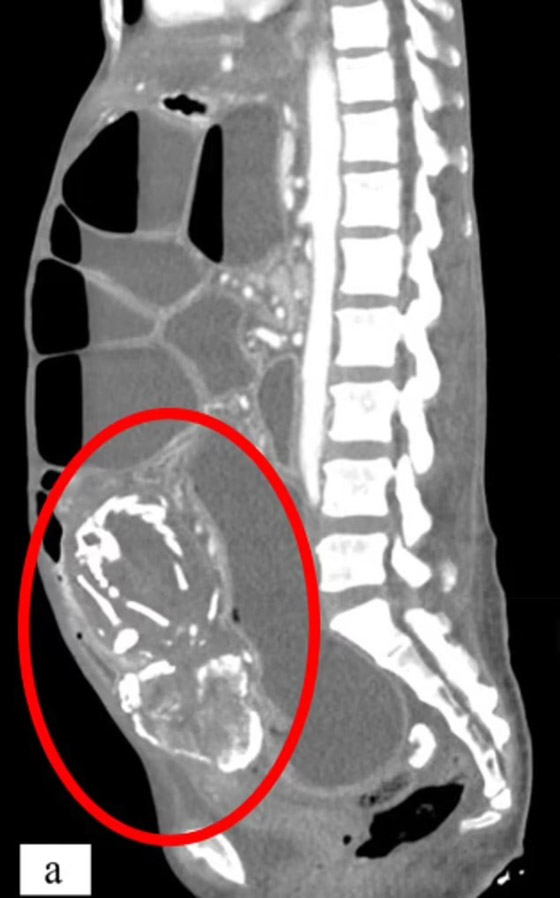

توفيت امرأة بسبب سوء التغذية الحاد بعد أن حملت جنيناً لم يولد بعد قرابة تسع سنوات داخل جسدها. وزارت المرأة، وهي في الأصل من الكونغو الأطباء في نيويورك وهي تشكو من تقلصات في المعدة وعسر الهضم وصوت غرغرة بعد تناول الطعام. وكشفت الفحوصات أن المرأة البالغة من العمر 50 عاماً لديها جنين متكلس ضغط على أمعائها، والذي يُعزى إلى إجهاض حدث قبل تسع سنوات.

الظاهرة النادرة، التي تم تسجيلها أقل من 300 مرة فقط، تحدث عندما يموت الجنين الذي ينمو خارج الرحم أثناء الحمل ولا يتم إطلاقه من الجسم. وهو من بين العديد من مضاعفات الحمل التي لها آثار طويلة الأمد على صحة الأم. ورفضت المريضة العلاج، قائلة إنها تعتقد أن حالتها الصحية مرتبطة بـ "تعويذة" ألقاها عليها شخص ما في إفريقيا. وتوفيت المرأة بعد 14 شهراً من وصولها إلى الولايات المتحدة. وقال الأطباء إنها ماتت من سوء التغذية الحاد أو الجوع.

وفي هذه الحالات، قد يكون سبب الوفاة في نهاية المطاف هو تدهور الأنسجة مما يؤدي إلى السكتة القلبية أو عدم انتظام ضربات القلب، وعدم انتظام ضربات القلب. وتشمل الأسباب الأخرى العدوى الناتجة عن ضعف جهاز المناعة. وبالنسبة لهذه المرأة، ظل "الطفل المتحجر" يضغط على الأمعاء. وتسبب هذا في انسداد أمعائها، مما يعني أن جسدها لم يعد قادراً على امتصاص العناصر الغذائية الحيوية. وقال الدكتور وسيم سوس، خبير الطب الباطني في جامعة ولاية نيويورك الطبية التي أبلغت عن الحالة، إن المريضة "رفضت التدخل خوفاً من الجراحة، ولسوء الحظ، توفيت بسبب سوء التغذية الحاد في سياق انسداد الأمعاء المتكرر والخوف المستمر من طلب الرعاية الطبية".

ولم يستطع الأطباء تحديد مكان حدوث الحمل في الجسم، لكنهم خلصوا إلى أنه من المحتمل أن يكون خارج الرحم. وعندما يموت الطفل، يكون حجمه أكبر من أن يمتصه الجسم مرة أخرى. ونتيجة لذلك، يقرر الجهاز المناعي أن الجنين الميت يشكل تهديداً للجسم. ويؤدي هذا إلى ترسب رواسب غنية بالكالسيوم على الجنين، وتغليفه تدريجياً بقشرة متكلسة أو تحويله إلى حجر. وتوقف الجنين - الذي كان من الممكن أن يكون الطفل التاسع للمرأة - عن النمو بداخلها في الأسبوع 28. لكن بدلاً من الإجهاض، عانت من الحالة المعروفة باسم lithopedion. وتحدث الحالة عندما يتكون الحمل في البطن بدلاً من الرحم. وفي هذه الحالة لا تصل كمية كافية من الدم إلى الطفل، مما يؤدي إلى فشل الحمل. ولا يستطيع الجسم طرد الجنين أيضاً، مما يؤدي إلى مضاعفات مميتة.